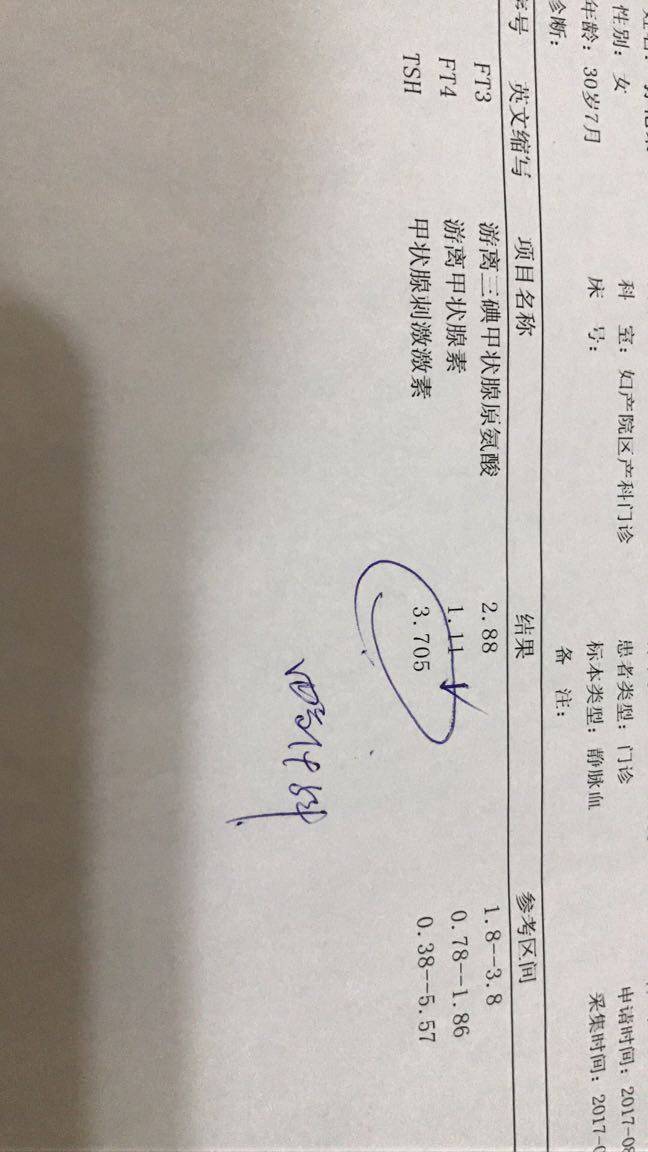

8月四号的时候医生给我开了七八百块钱的化验单,其中有一项是甲功三项,其他的检查我自己会看都没问题,甲功我也没看出问题,因为都在参考值内,可是今天医生看到了,就说这个不正常,让我进一步检查,今天走了一大天,实在是太累了,我等节后再去复查一下这个甲功

8月四号的时候医生给我开了七八百块钱的化验单,其中有一项是甲功三项,其他的检查我自己会看都没问题,甲功我也没看出问题,因为都在参考值内,可是今天医生看到了,就说这个不正常,让我进一步检查,今天走了一大天,实在是太累了,我等节后再去复查一下这个甲功

好像是怀孕,那个值要低于2.5比较好

我怀孕的时候就是偏高了,不正常,孕期甲减,吃药了